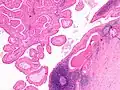

The appearance of this tumor under the microscope is unique. There are cystic spaces surrounded by two uniform rows of oncocytes, which are epithelial cells with abundant, granular, eosinophilic cytoplasm.[7] The cystic spaces have epithelium referred to as papillary infoldings that protrude into them. Additionally, the epithelium has lymphoid stroma with germinal center formation.

Histopathology of Warthin tumor in the parotid gland. H&E stain. -

Histopathology of Warthin tumor in the parotid gland. Another view of a file "Warthin tumor (1).jpg". H&E stain. -

Intermediate magnification micrograph of a Warthin tumor. -

High magnification micrograph of a Warthin tumor showing the characteristic bilayered epithelium.